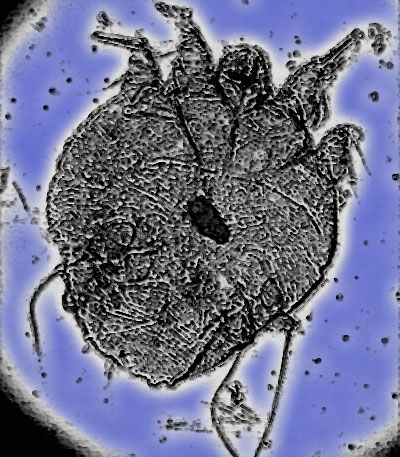

Sarcoptes scabiei, b) schéma du signe du Deltaplane, c) dermoscopie X : visualisation du sarcopte sous forme de deltaplane 24. En conclusion, il existe de nombreuses modifications de la peau pendant la grossesse sans danger et surtout qu’elles ne vous empêchent pas de vivre une grossesse sereine. Docteur DENJEAN qui a toujours conscience que la grossesse suppose une attention particulière du corps pendant la grossesse. Elle est due à un parasite qui pénètre la couche superficielle de la peau.